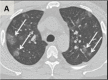

In this retrospective study, chest CTs of 121 symptomatic patients infected with coronavirus disease-19 (COVID-19) from four centers in China from January 18, 2020 to February 2, 2020 were reviewed for common CT findings in relationship to the time between symptom onset and the initial CT scan (i.e. early, 0-2 days (36 patients), intermediate 3-5 days (33 patients), late 6-12 days (25 patients)). The hallmarks of COVID-19 infection on imaging were bilateral and peripheral ground-glass and consolidative pulmonary opacities. Notably, 20/36 (56%) of early patients had a normal CT. With a longer time after the onset of symptoms, CT findings were more frequent, including consolidation, bilateral and peripheral disease, greater total lung involvement, linear opacities, "crazy-paving" pattern and the "reverse halo" sign. Bilateral lung involvement was observed in 10/36 early patients (28%), 25/33 intermediate patients (76%), and 22/25 late patients (88%).